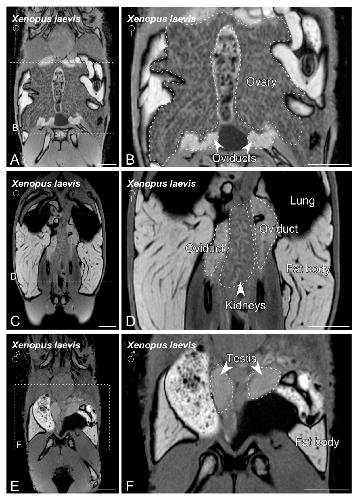

Sex Determination in Two Species of Anuran Amphibians by Magnetic Resonance Imaging and Ultrasound Techniques. , Ruiz-Fernández MJ, Jiménez S, Fernández-Valle E, García-Real MI, Castejón D, Moreno N , Ardiaca M, Montesinos A, Ariza S, González-Soriano J., Animals (Basel). November 18, 2020; 10 (11):